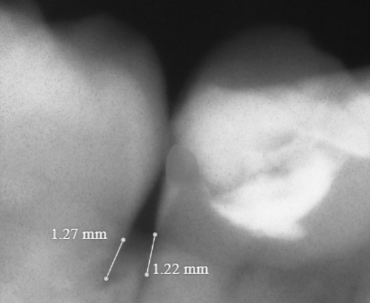

Ruler

- Click Ruler icon

to activate - Click starting point on the image and move the curser to desired measurement area

- Click again to end the measurement

- Click Ruler icon again to remove measurement and deactivate the tool

Click Save icon for the measurements to be saved as measure annotations (“measure line”) to the MWP viewer page

Once the Save button is clicked, all the measurements visible on the Pearl integration page to the MWP viewer page as annotations are saved.

If the image in MWP is not calibrated the measurements in the viewer will be shown in pixels rather than millimeters.

The maximum number of measurements are saved which matches the numbers in the Pearl viewer in case the detections are set to low.